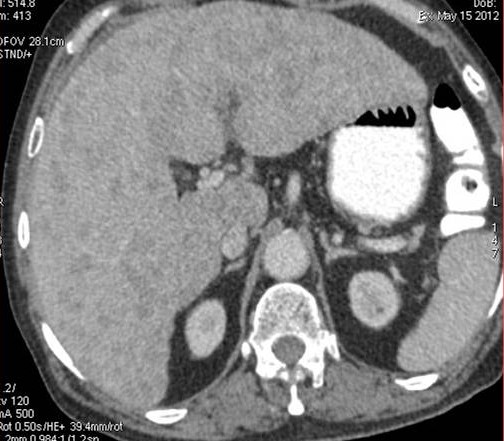

CT scan of the abdomen confirmed the findings ; For further clarification PET whole body scan was done at a centre in Chennai. The following images are from that.

Extensive FDG avid hepatic metastases involving both lobes.

The biopsy report of the liver secondary was a poorly differentiated carcinoma.

The oncologist advised palliative care and the patient passed away 3 weeks later.